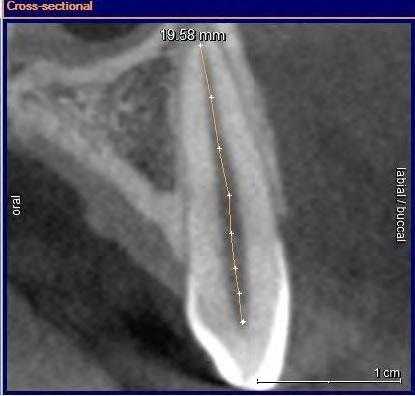

Рис. 5. Измерение расстояния от ЭЦГ до альвеолярного гребня в области зуба 2.3 (без рецессии). В данном случае показатели на 3 реформатах составили: 2,72; 3,04; 3,20 мм.

Рис. 6. Измерение расстояния от ЭЦГ до альвеолярного гребня в области зуба 1.3 (клиническая рецессия — 1,6 мм). В данном случае показатели на 3 реформатах составили: 4,28; 4,48; 4,64 мм.